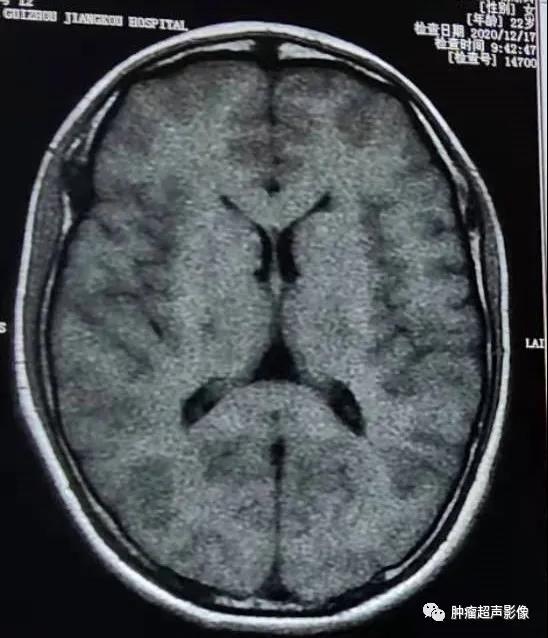

体检发现双肾多发错构瘤,双肾密集分布,考虑结节性硬化症表现,建议头颅检查(病例由江口县人民医院胡海英医师提供)

MR表现为两侧额枕叶皮层及皮层下多发结节或皮层增厚、脑回肥厚,FLAIR信号增高。

女,61,因肾肿瘤入院治疗,超声及CT示两肾多发错构瘤,建议头颅检查。

头颅CT示两侧侧脑室下多发小结节状钙化,增强MR示室管膜下结节明显强化。